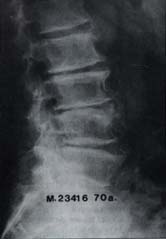

Estas zonas de transición son el resultado a su vez de los cambios morfológicos estáticos y dinámicos, determinados durante el desarrollo filogenético, ontogénico, de actividad y ocupación en la especie humana Figuras 1 y 2.

Fig 1. Espondiloartrosis de la región lumbosacra